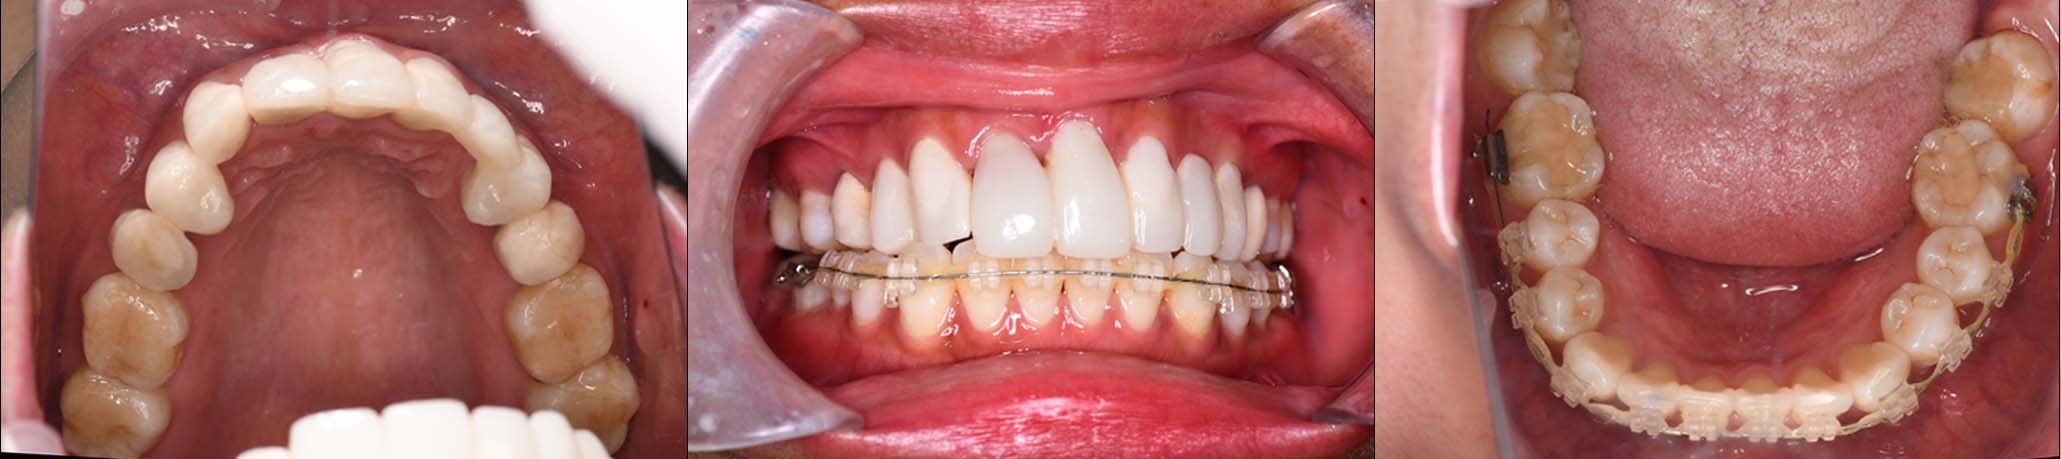

治療内容 ①スプリントを装着

②副子を装着

③2024年4月 口腔内反映開始

④副子を入れた状態の所まで咬合を挙上

(バイトアップ)

⑤2024年5月 上顎前歯部8本へ仮歯(TEK)

を装着

2024年 10月 下顎MTM開始